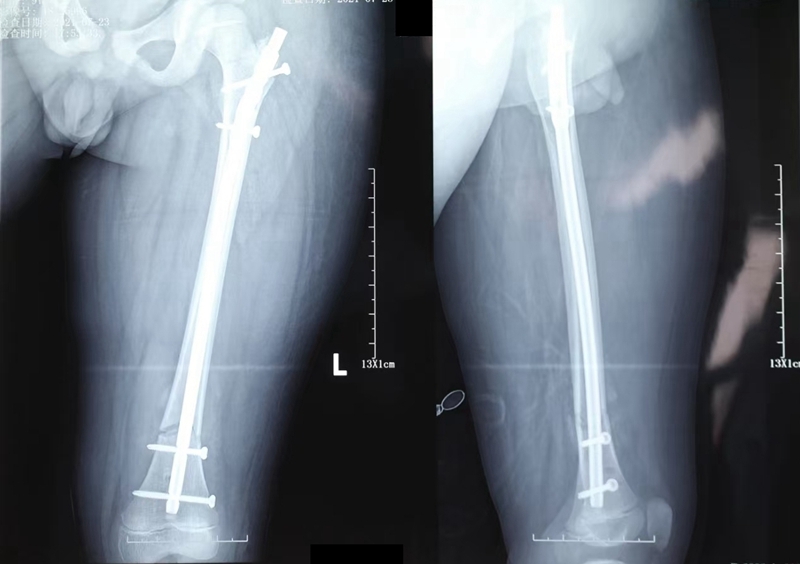

4.带锁髓内钉内固定:儿童股骨干骨折治疗的指南认为年龄大于10岁、体重大于49Kg的患儿建议使用带锁髓内钉。临床上对于大龄、大体重儿童股骨干骨折采用青少年股骨外侧髓内钉或带锁髓内钉内固定治疗,可取得良好的疗效,且安全性高。髓内钉内固定治疗也是一种微创手术方式,骨折断端一般不需要切口或做一小切口,就可达到解剖复位,带锁后可控制旋转,可以早期进行功能锻炼,对髋膝关节的活动影响较小。该方法也存在不足,有些病例会伴有股骨头坏死、髋外翻畸形和股骨颈狭窄等并发症。由于常常需要扩髓,导致髓内结构的遭到破坏,带锁引起骨折端应力遮挡,继而出现延迟愈合与不愈合,而最严重的并发症为股骨头缺血性坏死,虽然其发生率低,但这是影响其在临床广泛使用的原因,也是临床最严重的并发症。所以对于骨骼未成熟青少年,不推荐使用交锁髓内钉。但是也有学者治疗青少年股骨干骨折选用青少年型带锁髓内钉时,经大转子外侧进针,在短期内对股骨头血运、股骨近端骨骺发育和髋关节功能不会造成影响。

带锁髓内钉治疗儿童股骨干骨折